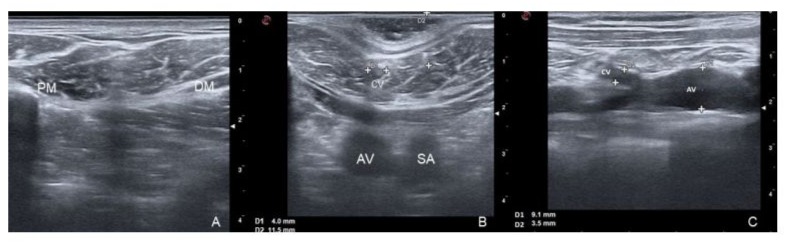

The CV was classified by its size into absent (when not visible), small (diameter < 3.0 mm) and normal (diameter ≥ 3.0 mm). This classification is used because the TIVAP implantation system is a NuPport HP* device (PHS MEDICAL - Fuldabrück, Germany) with a single-chamber titanium port and a silicone catheter with an external diameter of 9.6 F (≈ 3.0-3.2 mm). CV stenosis is defined as a narrowing of the vessel lumen of more than 50% of the total. The absence of flow signals in the AV with intraluminal echogenic material is considered as venous thrombosis. Figure 1 shows the different parameters assessed in this study.

Figure 1: Ultrasound findings in the DG; 1A: Cephalic Vein (CV) absent in the DG (located between Pectoralis Major Muscle [PM] and Deltoid Muscle [DM]); 1B: CV diameter (D1) and CV depth (D2); Cross-sectional view of Axillary Vein (AV) and Subclavian Artery (SA); 1C: confluence of the CV into the AV.